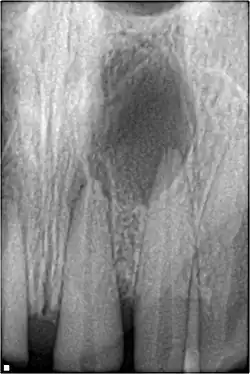

Radiographic signs of periapical inflammation is usually evident in a tooth with necrotic pulp

Pulp necrosis usually occurs either as ischaemic necrosis (infarction) caused by disruption to the blood supply at the apical foramen or as an infection-related liquefactive necrosis following dental trauma (2). Signs of pulpal necrosis include[42]

• Radiographic signs of periapical inflammation